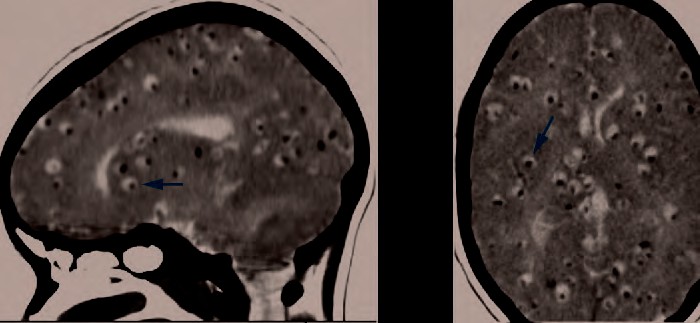

Figure 26.13 (a) A false color TEM of a mosquito salivary gland cell shows an infection of the eastern equine encephalitis virus (red). (b) CT (left) and MRI (right) scans of the brains of children with eastern equine encephalitis infections, showing abnormalities (arrows) resulting from the infection. (credit a, b: modifications of work by the Centers for Disease Control and Prevention)